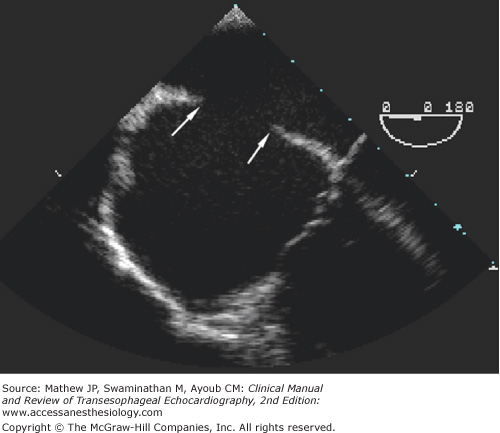

Figure 18-9.

A sinus venosus defect in the posterior portion of the interatrial septum near the entrance of the superior vena cava is often best visualized with the bicaval view. A central venous catheter is seen passing through the superior vena cava into the right atrium. Arrows point to the margins of the defect. (LA, left atrium; RA, right atrium; SVC, superior vena cava.)